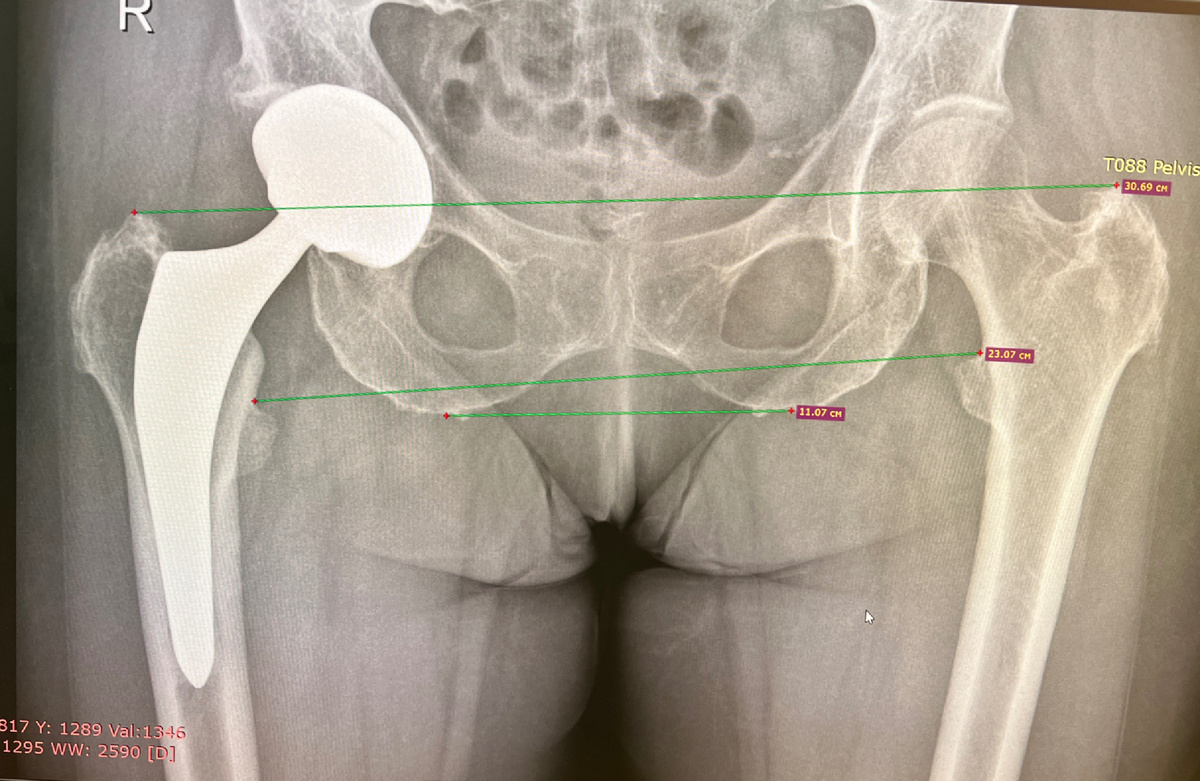

Женщине 70 с хвостиком около 10 лет назад я оперировал обе стопы. Всё хорошо, никаких проблем. Год назад понадобилось заменить тазобедренный сустав. По разным причинам поехала в другой город, к хорошему хирургу, отличный швейцарский протез. Модный передний доступ. И сначала всё было хорошо, правда, приходилось под здоровую ногу подкладывать подпяточник 3 сантиметра, потому что на операции ногу удлинили.

Не на три, конечно, а в пределах двух, но при росте 160 сантиметров это существенная разница.

Потом появились боли сбоку таза. Хирург отмахивается - с протезом всё хорошо, эти боли - в голове. На самом деле, конечно, нет. Боли являются следствием удлинения ноги….